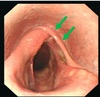

Diagnosis and grade

Fig 1. HST photographs of larynges illustrating 3 grades of ADAF. (A) Mild ADAF: axial collapse of both aryepiglottic folds remains abaxial to the vocal cords. (B) Moderate ADAF: the aryepiglottic folds have collapsed to a point less than halfway between the vocal cords and the midline. (C) Severe ADAF: both aryepiglottic folds have collapsed more than halfway between the vocal cords and the midline.